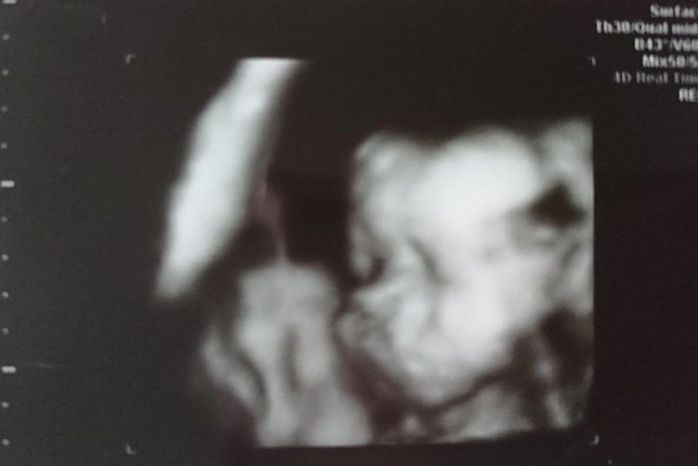

妊娠33週目のエコー写真

おなかが大きくなり、胃を圧迫してあまり食べられなくなってきました。大きなおなかでの通勤はかなり厳しく、産休に入るのを指折り数えていた日々でした。電車で席を譲ってもらえたり、会社で周囲の人が気遣ってくれたのがとても嬉しく、人の温かさに救われていた時期でした。夜中におなかの中で動き回るので、寝不足になっていた時期です。赤ちゃんの推定体重は2213gでした。

やっと産休に入り、体を休める事ができた幸せな時期でした。時間に余裕ができたので、少しずつ男の子の名前を考えていました。予定の帝王切開の手術まで1カ月あるので、まだ出産の準備はしていませんでした。まさか次の妊婦健診の日に産む事になるとは、夢にも思っていませんでした。赤ちゃんの推定体重は2493gでした。